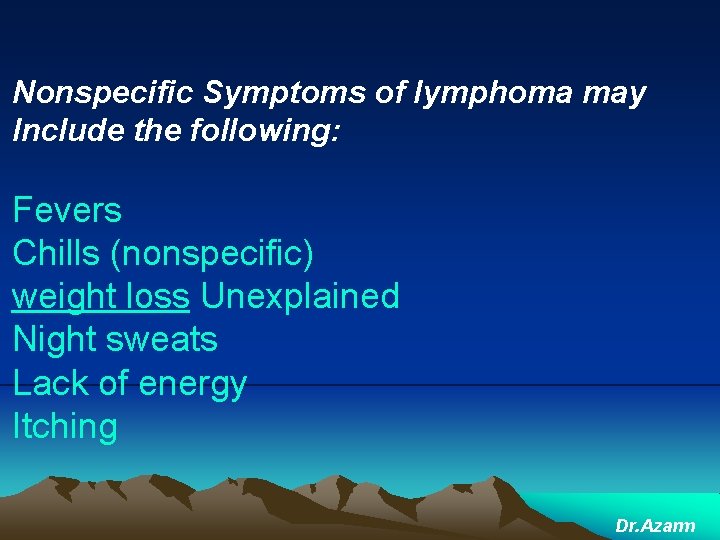

Nonspecific Symptoms of lymphoma may Include the following: Fevers Chills (nonspecific) weight loss Unexplained Night sweats Lack of energy Itching Dr. Azarm